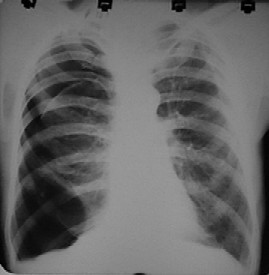

Click Imagen Ampliada

Fig. Masculino. 22 años. APP: asmático. MC: dolor torácico izquierdo. Neumotórax izquierdo con colapso pulmonar casi total.